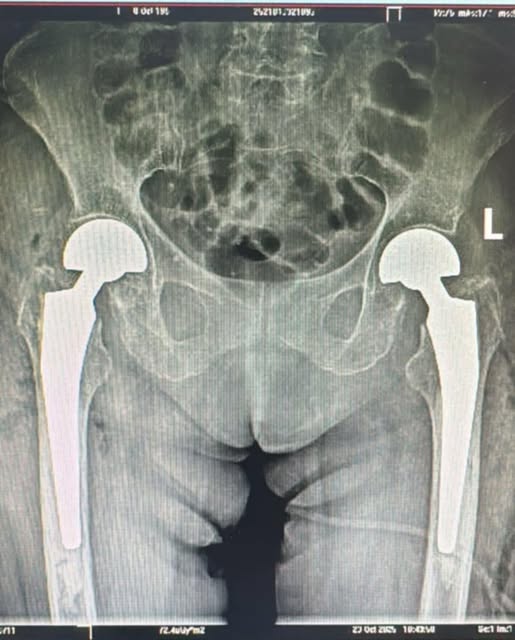

Echipa Secției Ortopedie-Traumatologie a realizat, în premieră pentru Spitalul Clinic Judeţean de Urgenţă Sibiu și pentru județul Sibiu, o intervenție chirurgicală complexă: artroplastie parțială de șold bilateral, efectuată în același timp operator.

Pacienta, în vârstă de 73 de ani, a ajuns în UPU cu dureri intense și imposibilitatea de a se deplasa. Investigațiile au arătat o fractură bilaterală de col femural, o patologie gravă și extrem de rar întâlnită, se arată într-o postare făcută pe pagina de Facebook a spitalului menționat. După pregătirea preoperatorie, echipa medicală a decis intervenția simultană pe ambele șolduri – o procedură cu un grad ridicat de dificultate.

Operația a fost un succes, iar evoluția pacientei este favorabilă. În prezent, se află în proces de recuperare și se poate deplasa.